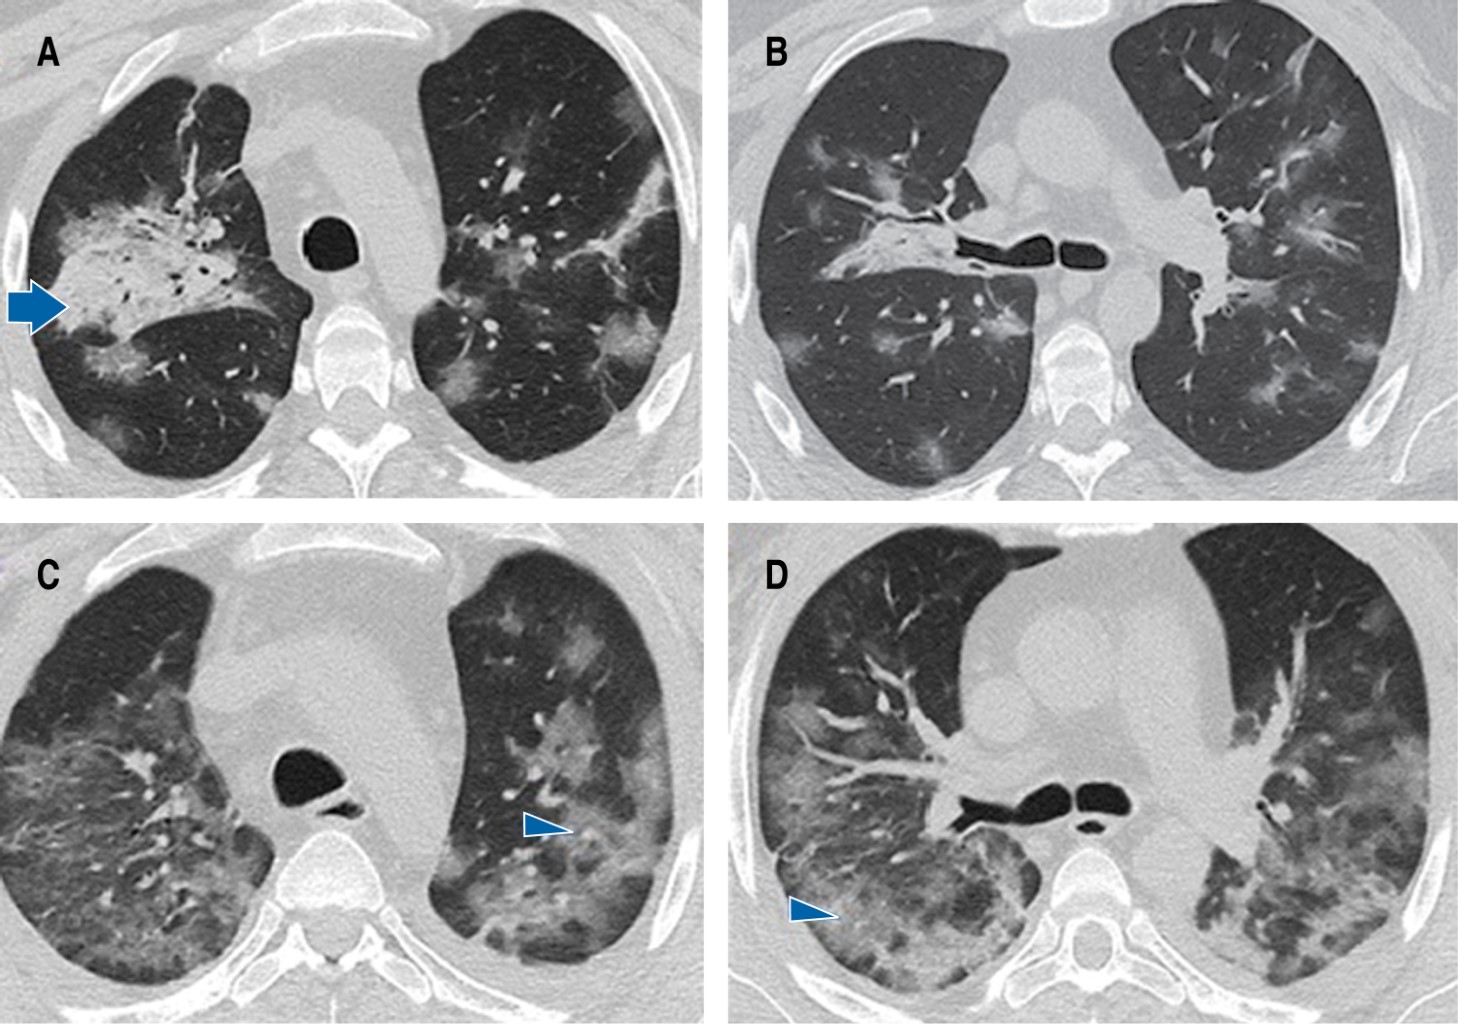

A 36-year-old man with a history of related living donor renal transplantation (2003) for bilateral renal hypoplasia presented humoral rejection in November 2021 and required immunosuppressive management with rituximab, to later receive mycophenolate, prednisone and tacrolimus, conditioning hematologic toxicity and severe immunosuppression. He also suffers from secondary systemic arterial hypertension, in treatment with calcium antagonist and angiotensin II converting enzyme inhibitor. He was admitted for a clinical picture of four days of evolution characterized by fever of 39 oC, dysgeusia, anosmia, cough, myalgias and arthralgias, accompanied by progressive dyspnea up to modified Medical Research Council (mMRC) 4 and pulse oximetry saturation (SpO2) of 88%. On admission to the emergency room he had blood pressure: 105/65 mmHg, heart rate: 85 bpm, respiratory rate: 29 rpm, temperature: 36.7 oC, SpO2: 87%, arterial blood gas (ABG) arterial oxygen pressure (PaO2): 57.6 mmHg, arterial carbon dioxide pressure (PaCO2): 36.6 mmHg, pH: 7.43, arterial oxygen pressure/inspired oxygen fraction index (PaO2/FiO2): 274 mmHg. Chest computed tomography scan confirmed the presence of ground glass areas of random distribution both peripherally and centrally affecting more than 60% of the lung parenchyma (Figure 1A and 1B), and also revealed pancytopenia. Polymerase chain reaction retrotranscriptase (PCR-RT) test for SARS-CoV-2 in nasopharyngeal exudate was positive. Supportive treatment, dexamethasone 6 mg every 24 hours and prophylactic anticoagulation with enoxaparin was initiated. However, 24 hours after hospital admission he developed severe acute respiratory failure syndrome (PaO2/FiO2: 49.4 mmHg) and septic shock. A second simple chest computed tomography scan was performed, which showed significant extension of the pneumonia (Figures 1C, 1Dand 2), so he was admitted to the intensive care unit (ICU) for advanced airway management and assisted mechanical ventilation. Due to clinical and radiological deterioration and because he was a patient with hematologic toxicity due to immunosuppressants, bronchioloalveolar lavage was performed and CMV was identified by polymerase chain reaction/ complementary deoxyribonucleic acid (PCR/cDNA) for cytomegalovirus: 554 copies/mL. The patient's clinical course was torpid, requiring vasoactive amines and renal function replacement therapy. However, after the administration of valganciclovir 900 mg every 24 hours for 21 days, together with the rest of the treatment, the evolution was favorable. Percutaneous tracheostomy was performed due to muscle weakness and prolonged mechanical ventilation; mechanical ventilation was withdrawn after 26 days of stay in ICU, and renal function was recovered, which allowed suspending renal function replacement therapy. The patient was discharged from the hospital five days later with supplemental oxygen 2 L/minute and physical and respiratory rehabilitation. Swallowing test and endoscopic revision of the airway were performed 10 days after discharge, in which malacia and stenosis were ruled out, and the tracheostomy tube was removed.